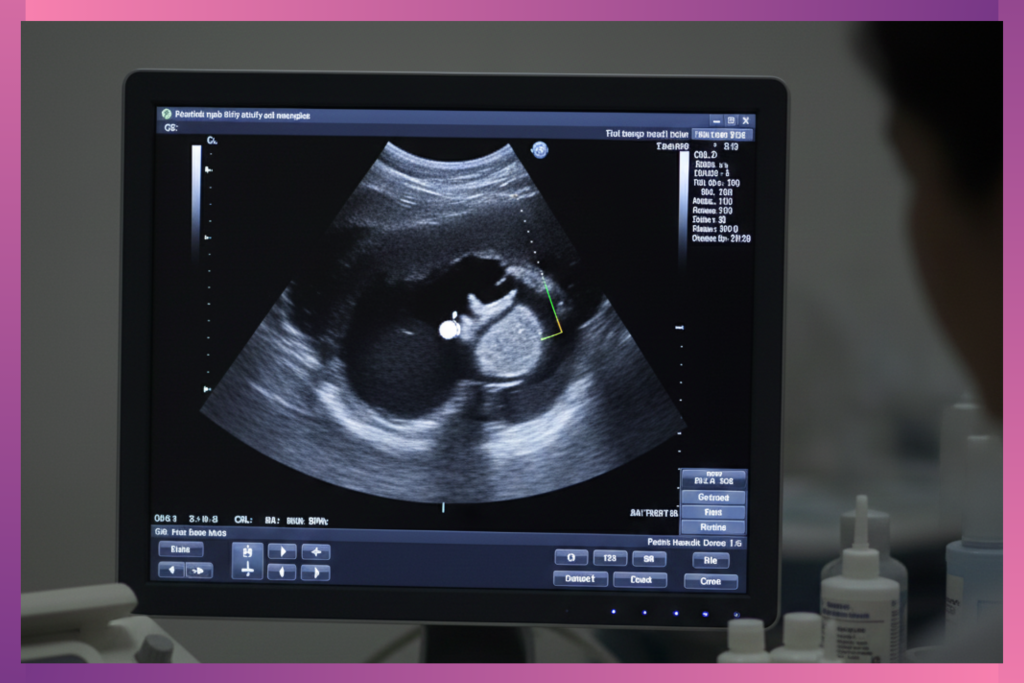

At 4 weeks, your uterus is still tucked deep in your pelvis, and the gestational sac is about the size of a poppy seed. A regular abdominal ultrasound won’t pick it up yet. (I’m getting deja vu feeling right now… I feel like I have said this somewhere, perhaps I have written it in another article of mine somewhere but nevertheless…).

It’s like trying to spot a single grain of rice at the bottom of a deep bowl. That’s why providers use a transvaginal probe. It gets closer to your uterus, giving a clearer image. I saw the relief on my friend’s face when the sonographer explained to her: “This isn’t because something is wrong, It’s because we want the clearest picture of your tiny poppy seed”, he told her.

What They’re Actually Looking For on the Screen

The gestational sac: A tiny black bubble (fluid-filled) nestled in the thickened uterine lining.·

The yolk sac: A small white ring inside the gestational sac — the baby’s first lunchbox.· Location: To rule out ectopic pregnancy (sac forming in the wrong place, like a fallopian tube).